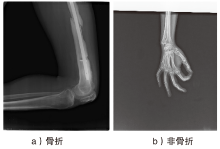

随着智能医疗系统的快速发展,标注数据的匮乏已成为制约研究进展的关键因素之一,知识蒸馏作为一种有效的数据利用策略能够缓解这一问题。然而,在智能医疗领域,模型通常用于替代人工进行影像、数据的诊断,这不仅对医疗信息隐私保护提出了更高要求,还强调了模型精度对诊断结果准确性的决定性影响。因此,文章提出一种结合差分隐私的知识蒸馏方案,并将其应用于图神经网络模型,在知识蒸馏过程中保护用户敏感信息的同时,确保较高的医疗诊断准确率。为验证所提方法的有效性,文章构建了图注意力网络(GAT)模型和卷积神经网络(CNN)模型作为对照组,并采用3种实际医疗图像数据集进行实验。结果表明,文章所提方法在GAT模型的准确率较在CNN模型的准确率有所提升,对应在3个数据集上分别由61%提升至68%、83%提升至93%、67%提升至80%。鉴于GAT模型的高资源开销,文章进一步设计了一种轻量化GAT模型架构。该轻量化模型在显著降低资源消耗的同时,仍保持优于CNN模型的分类性能,从而在差分隐私保护的前提下,有效提升医疗诊断效果。